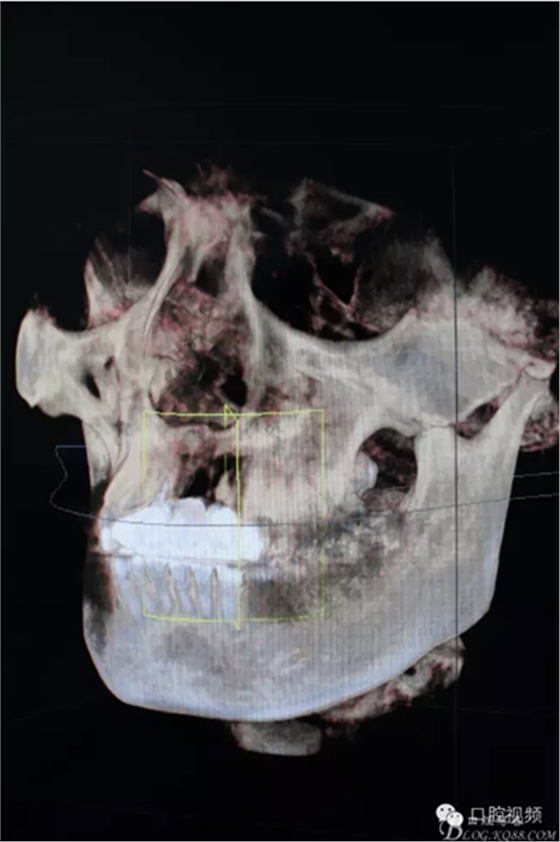

圖4.CBCT三維影像檢查:21區(qū)域牙槽骨完全喪失、并波及22區(qū)域。